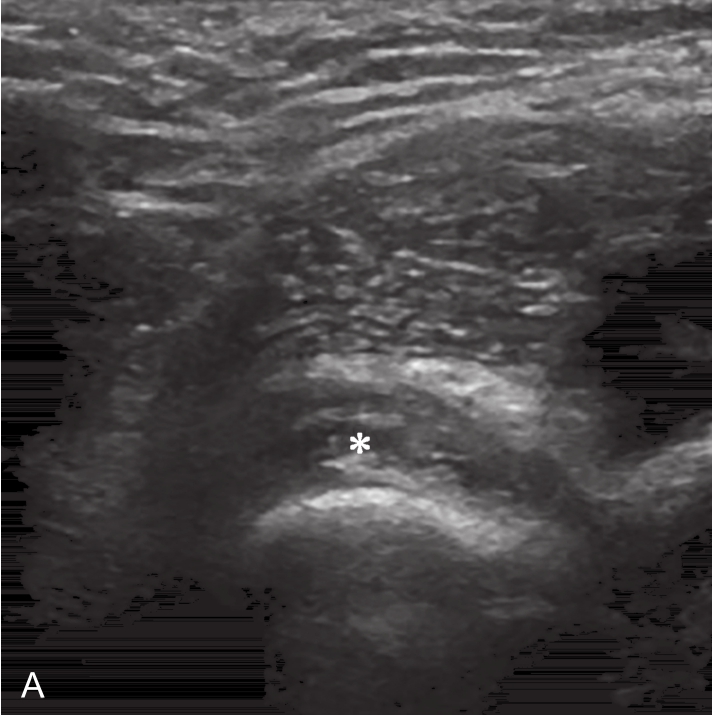

▲ 图2-6-3 超声引导下肩关节腔介入治疗超声图(一)

A、B.二维超声显示肩关节腔少量积液,滑膜增厚;C.超声引导针尖进入关节腔;D.超声示意图,虚线蓝色区域:后关节腔;单星号:腋下关节囊;双星号:后关节腔;短箭头:穿刺针;长箭头:穿刺针路径;L:盂唇;HH:肱骨头